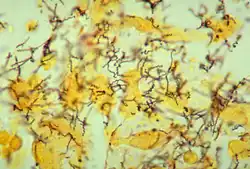

Treponema pallidum, poddruh pallidum, je spirálovitá, gramnegativní, vysoce pohyblivá bakterie.[9][14] Poddruhy příbuzné Treponema pallidum způsobují další tři lidská onemocnění, mezi něž patří frambézie (poddruh pertenue), pinta (poddruh carateum) a endemická syfilis (poddruh endemicum).[5] Oproti poddruhu pallidum však nejsou příčinou neurologických onemocnění.[13] Lidé jsou jediným známým přirozeným rezervoárem poddruhu pallidum.[6] Bez hostitele není tento poddruh schopen přežít déle než několik dnů, a to vzhledem ke svému malému genomu (1,14 MDa), který nedokáže zakódovat metabolické dráhy k většině makronutrientů. Má pomalou dobu zdvojení, která je delší než 30 hodin.[9]

Pro stanovení okamžité diagnózy z šankru lze využít mikroskopické vyšetření serózní tekutiny na tmavém poli. Nemocnice však vždy nemají potřebné vybavení nebo zkušený personál – test totiž musí být proveden do 10 minut od odebrání vzorku. Senzitivita je téměř 80 %, lze ji tudíž využít pouze pro potvrzení diagnózy, ne pro její vyloučení. Na vzorku z šankru lze provést další dva testy: přímý fluorescenční test na přítomnost protilátek a test amplifikace nukleových kyselin. Přímé fluorescenční testování využívá protilátek označených fluoresceinem, které se vážou na specifické bílkoviny syfilidy, zatímco amplifikace nukleových kyselin používá k odhalení přítomnosti konkrétních genů syfilidy technik jako například polymerázová řetězová reakce. Tyto testy nejsou tak citlivé na časové hledisko, jelikož pro stanovení diagnózy nevyžadují živé bakterie.[9]